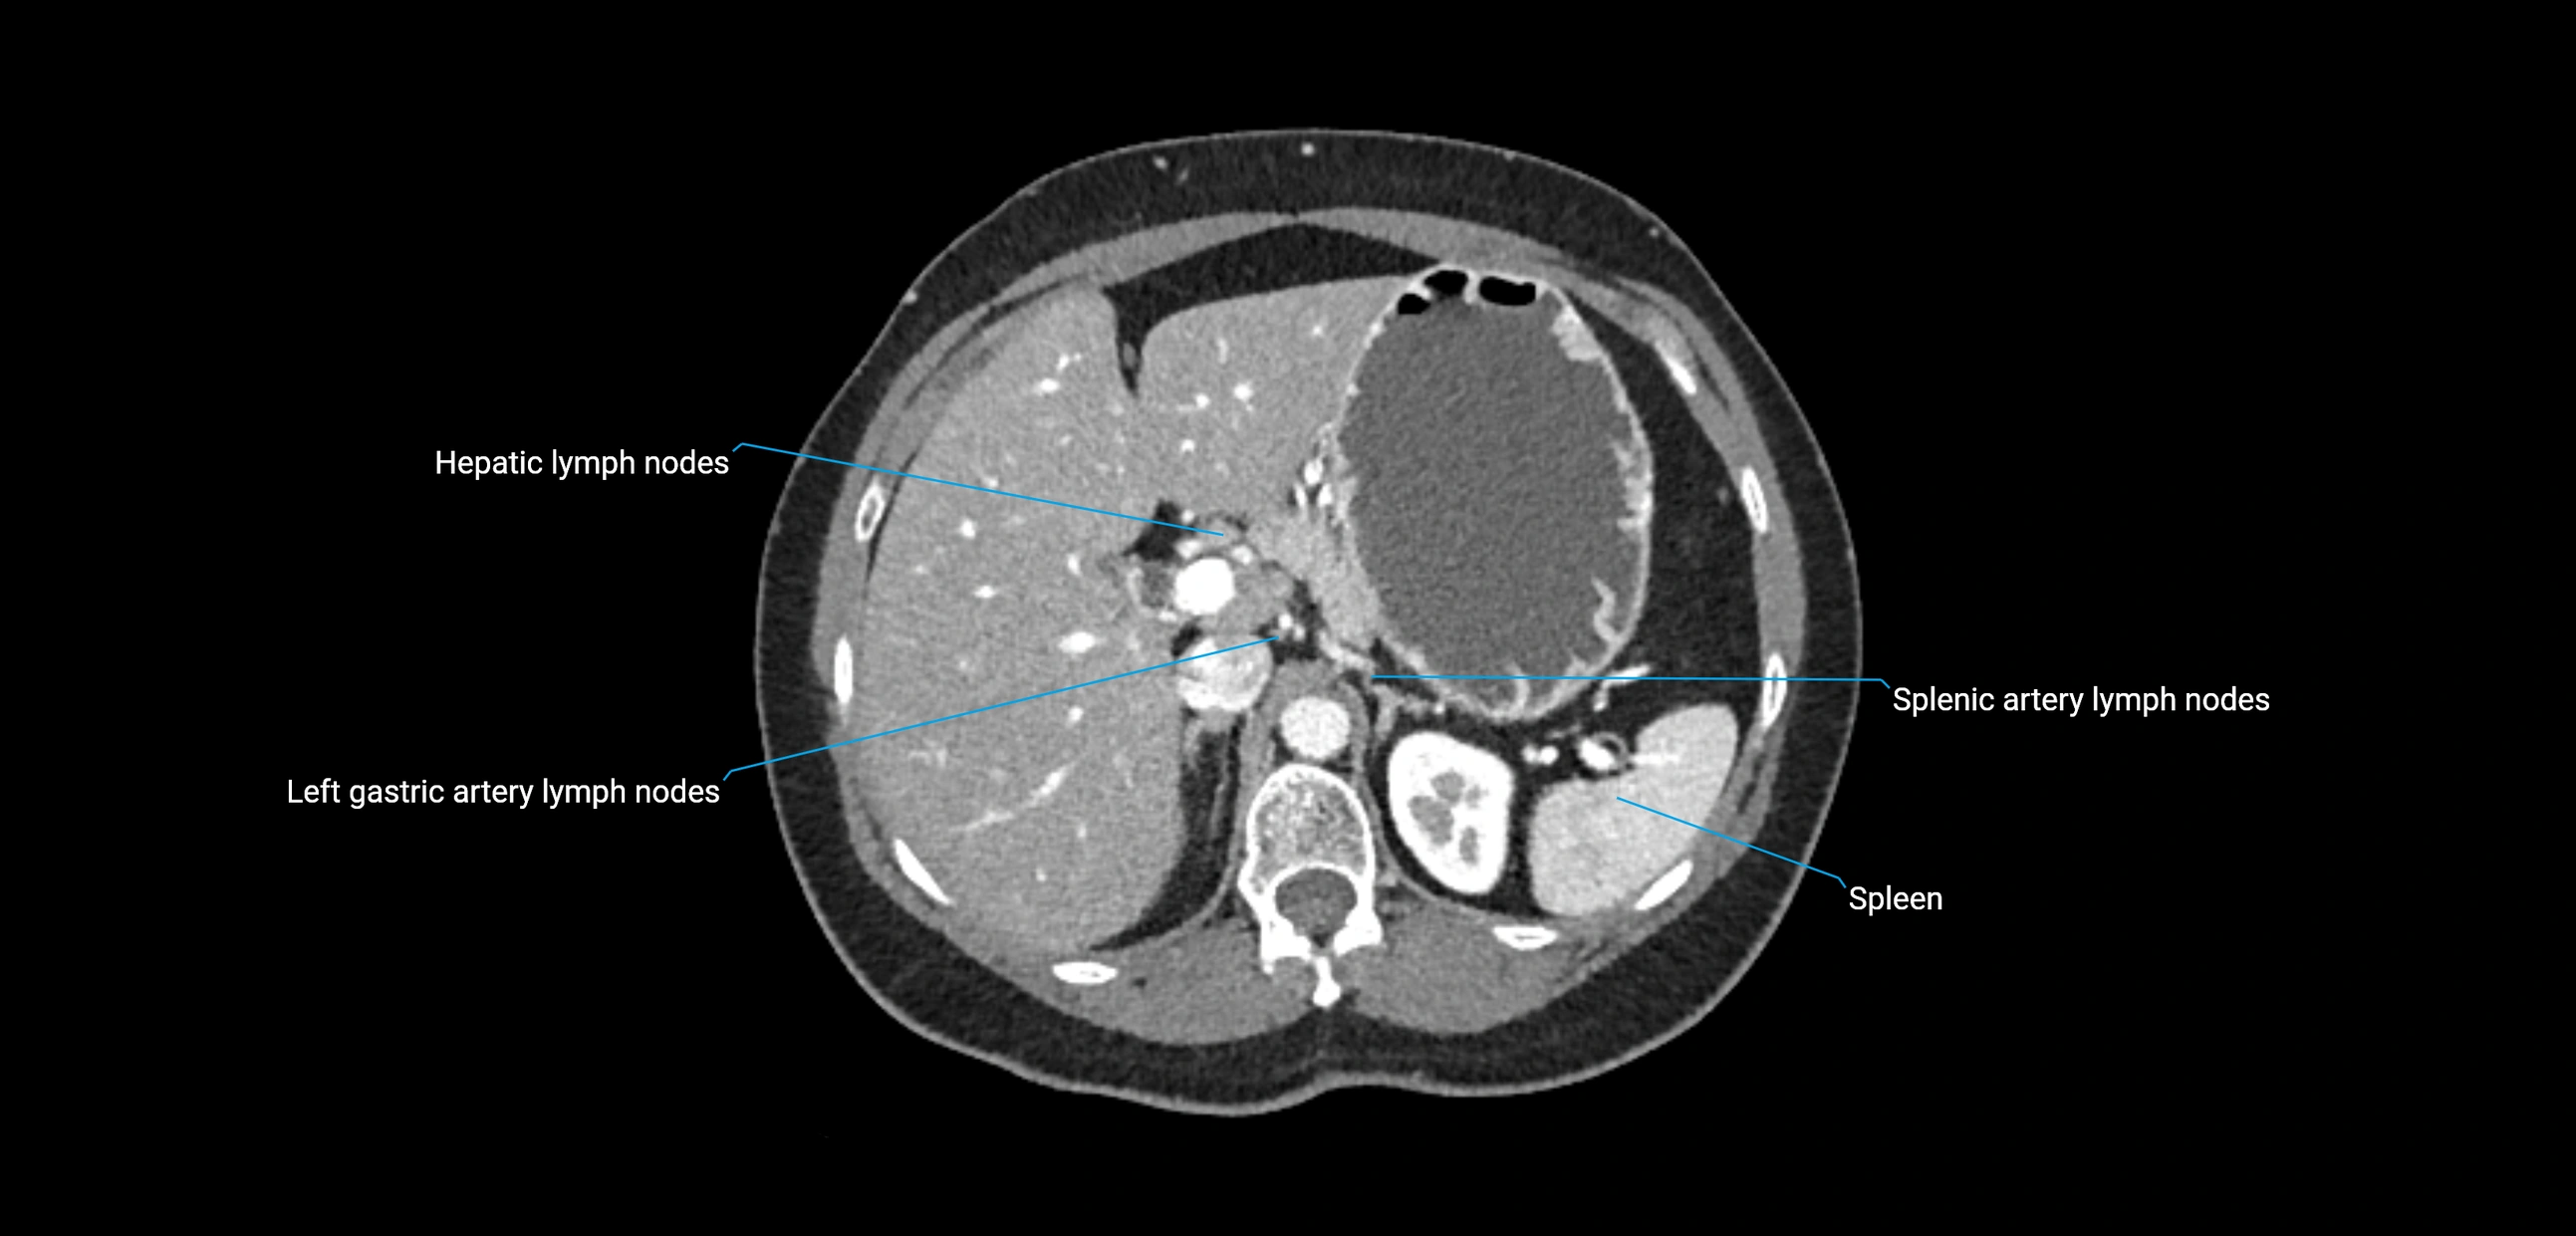

CT image

image